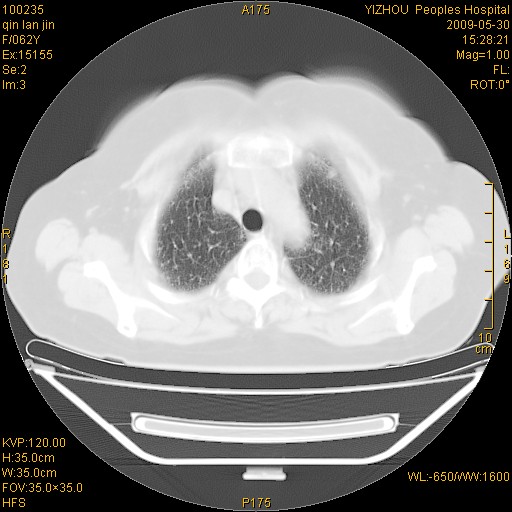

标题: CT20268:肺泡癌?间质性肺炎? [打印本页]

标题: CT20268:肺泡癌?间质性肺炎?

女,62岁,近二年经常咳嗽,近二个月,消瘦、乏力。

弥漫性双肺间质纤维化。

两肺弥漫性间质性病变(间质性肺炎伴肺间质纤维化?)。

弥漫性双肺间质纤维化

间质性肺炎伴肺间质纤维化。